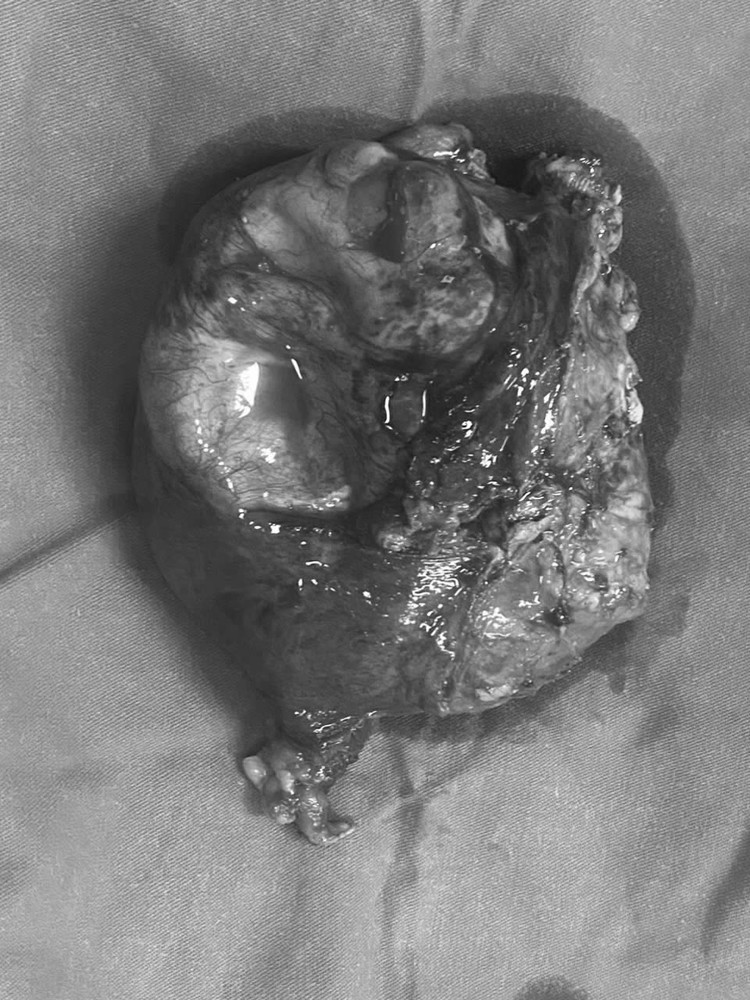

Sau khi làm các xét nghiệm chẩn đoán, chỉ điểm khối u, chụp cắt lớp vi tính ổ bụng nội soi dạ dày, đại tràng, các bác sĩ chẩn đoán bệnh nhân bị khối u quái buồng trứng phải, theo dõi K buồng trứng.

Khối u rất lớn kích thước trên 15cm đã chèn ép nhiều cơ quan, cộng thêm bệnh nhân có rất nhiều bệnh lý nền: Đái tháo đường, tăng huyết áp, viêm gan B, C, COPD, suy thận, nếu không phẫu thuật kịp thời, nguy cơ ảnh hưởng trực tiếp đến tính mạng. Vì vậy các bác sĩ đã khẩn trương tiến hành thực hiện phẫu thuật.

Theo các bác sĩ, đây là một ca phẫu thuật khó vì bệnh nhân nhiều bệnh lý nền, mặt khác khối u kích thước lớn đã làm biến đổi giải phẫu các cấu trúc trong tiểu khung như: Niệu quản, bàng quang, trực tràng, động mạch chậu… Ngoài ra, khối u này lại giàu mạch máu nuôi dưỡng nên nguy cơ chảy máu rất cao, gây nhiều khó khăn trong việc phẫu thuật.

Các bác sĩ đã phải thực hiện phẫu tích tỉ mỉ, bóc tách và bảo tồn được các cấu trúc quan trọng trong cuộc mổ. Sinh thiết tức thì cho kết quả ung thư buồng trứng, Ekip phẫu thuật đã tiến hành cắt toàn bộ, hai phần phụ kèm mạc nối lớn, ruột thừa và khối u.

Sau 3 giờ phẫu thuật ca phẫu thuật diễn ra thành công loại bỏ triệt để các tổn thương ung thư, bệnh nhân được chăm sóc, điều trị hậu phẫu tích cực.

Kết quả giải phẫu bệnh phẩm sau phẫu thuật xác định ung thư biểu mô dạng nội mạc. Hiện tại, sức khỏe bệnh nhân ổn định, tiếp tục quá trình điều trị hóa trị bổ trợ.